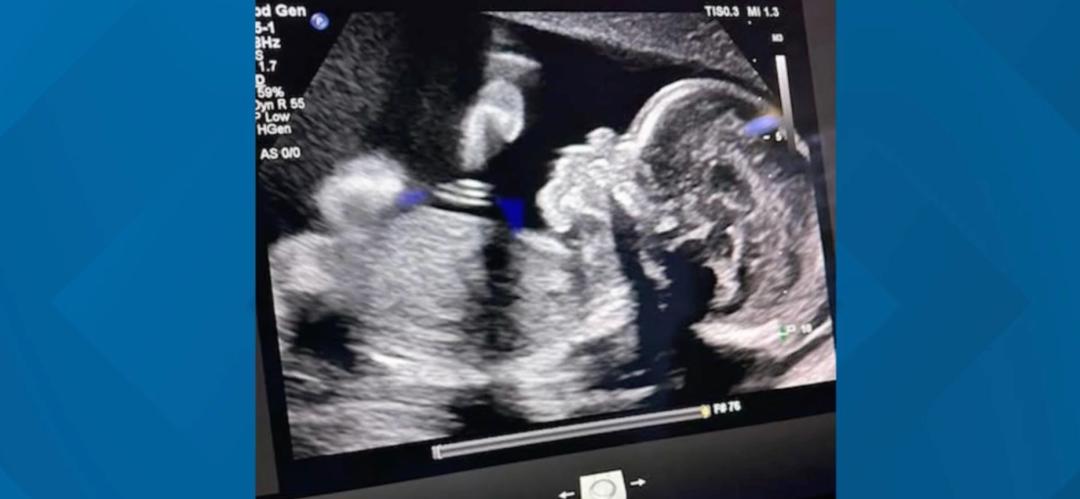

但问题是,史密斯这时候已经怀孕大概9周了。

家人给这个新生儿取名叫“Chance机会”,意思是得到了活着的机会。实际上在Chance出生之前,健康状况就很让人担心啊,他有脑部积液,可能先天就会失明或者没法行走。